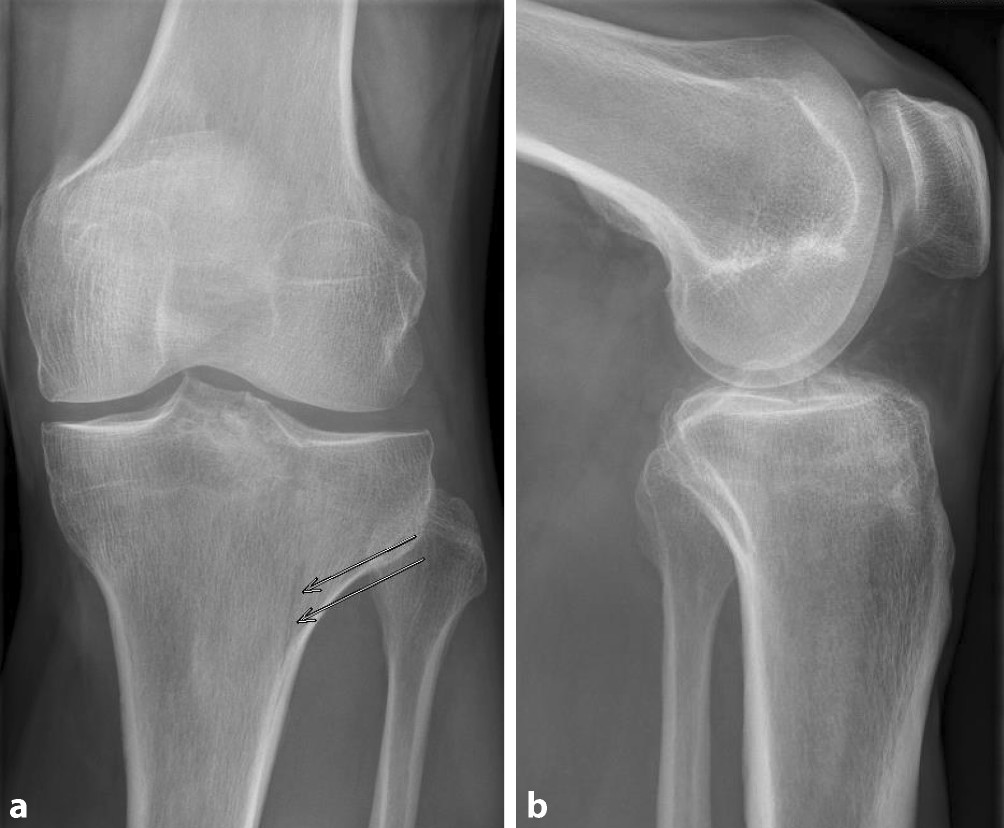

Abb. 1

Röntgenaufnahme in a.p. (a) und lateraler Ansicht (b) einer lateralen Tibiaplateaufraktur AO (Arbeitsgemeinschaft Osteosynthese) 41B1.1 (Pfeile). Aufgrund der geringen Dislokation bei Spaltbrüchen ist die nativradiologische Diagnostik nicht zuverlässig

Tibiaplateaufrakturen präsentieren sich klinisch mit großer Varianz. Traditionell erfolgte die nativradiologische Darstellung in anterior-posteriorer (a.p.) sowie seitlicher Ansicht (Abb. 1). Die so angefertigten Einzelaufnahmen erlauben jedoch keine exakte Beurteilung des 3‑dimensionalen Frakturcharakters und eine entsprechende Planung der operativen Strategie, insbesondere bei komplexen Frakturen. Die Reliabilität der nativradiologisch klassifizierten Tibiaplateaufrakturen wurde als schlecht oder mäßig bewertet [3, 4]. Die a.p. und laterale Aufnahme haben dabei eine Sensitivität von 79 % in der Diagnostik von Tibiaplateaufrakturen (Abb. 1; [8, 19]).

Diese Ergebnisse sowie die flächendeckende Verfügbarkeit qualitativ hochwertiger Computertomographen haben die native CT-Bildgebung bei Tibiaplateaufrakturen als Goldstandard bei der Diagnostik und präoperativen Planung etabliert. Insbesondere bei der Diagnostik koronarer Frakturlinien, die bei komplexen Tibiaplateaufrakturen mit einer Inzidenz von 30–39 % auftreten, zeigt sich das CT im Gegensatz zum klassischen Röntgen führend, da diese konventionell radiologisch häufig nicht erkannt werden (Abb. 1 und 2; [2, 3, 21]).